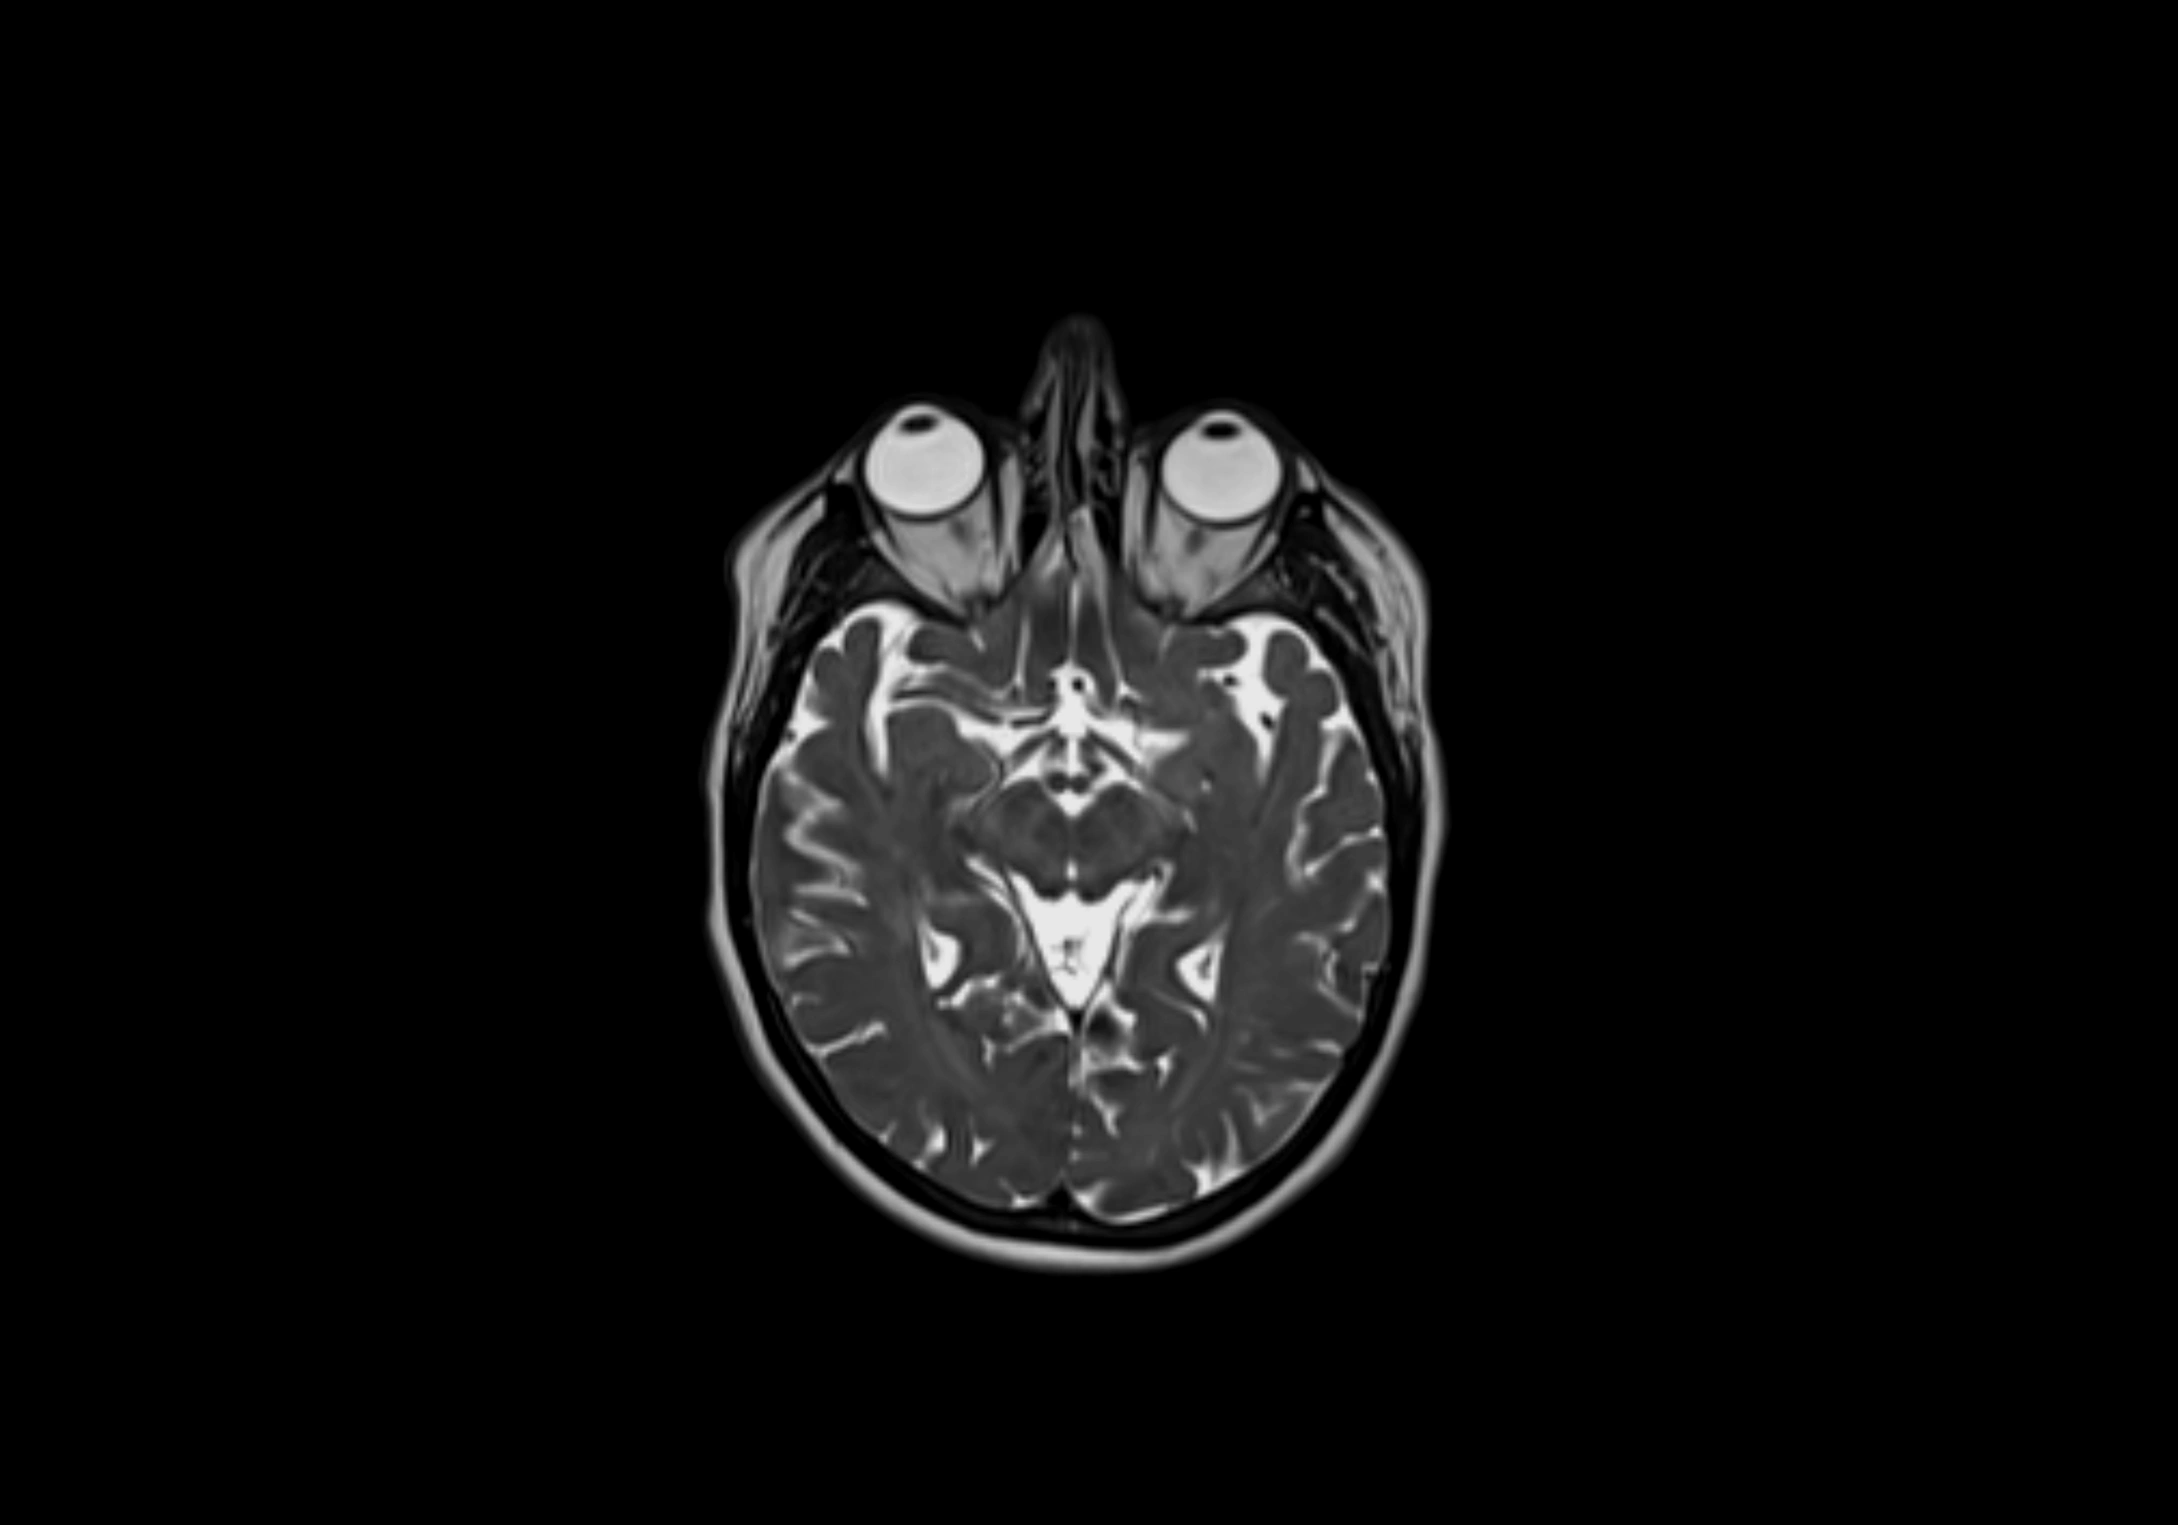

T2-weighted images:

• Nodes show intermediate signal, with surrounding fat bright

• Useful for detecting edema, inflammation, or infiltration

• Fatty hilum may appear slightly hyperintense relative to cortex